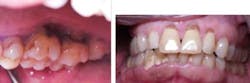

Case No. 1 — Mrs. High Anxiety

A 67-year-old African American female presented in 2001. Her diagnosis was chronic periodontitis and diabetes. Fear and anxiety resulted in refusal of osseous surgical care for bone regeneration and pocket reduction. Scaling was performed and the patient did not return for five years. She then presented with an abscess on No. 9 with significant bone loss that was not evident five years ago. Tooth No. 9 tested vital. The patient accepted the LANAP protocol. Treatment was done in January 2012.

Mrs. High Anxiety before the LANAP protocol.